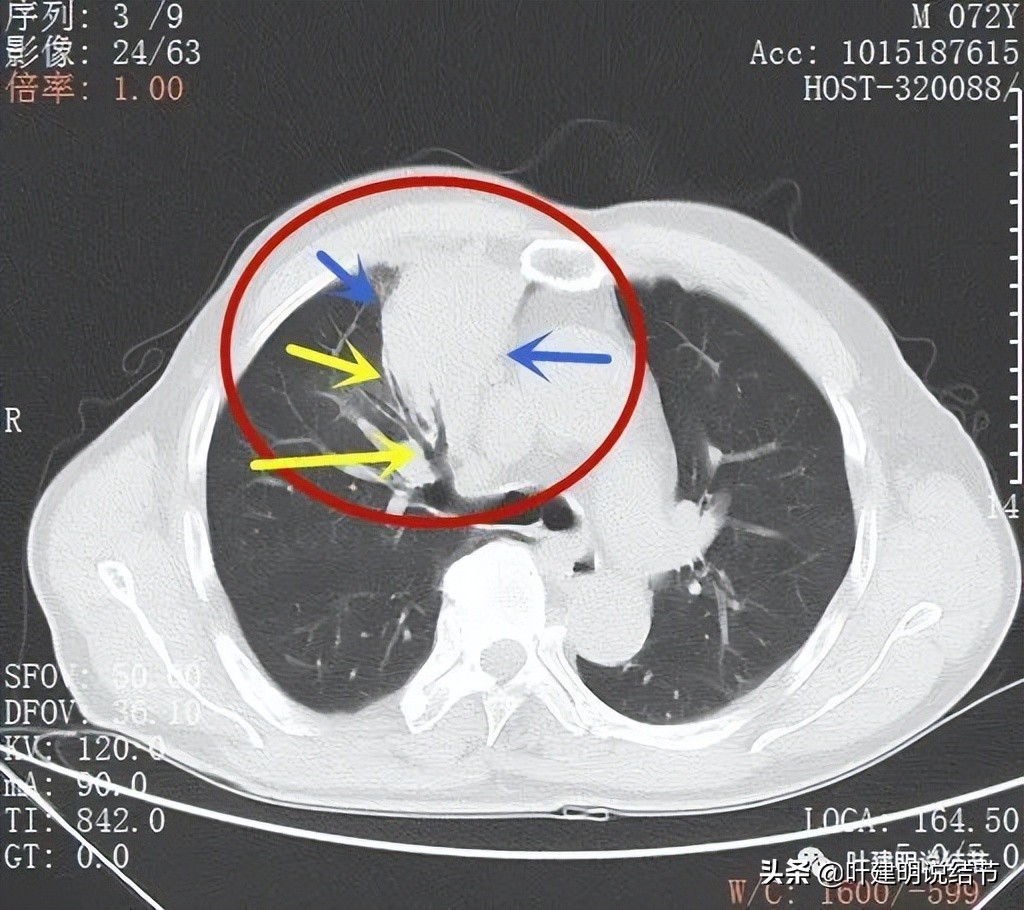

肿瘤位于上叶,实性,此层感觉有膨胀性;但边缘毛刺是不明显的,感觉偏光滑了点(蓝色箭头)

纵隔侧病灶没有推压纵隔组织,边缘相对平直(红色箭头),胸肋侧也是边缘较为光滑(蓝色箭头)

因为肿块巨大,整体看有些层面还是有鼓鼓的感觉的(红色箭头),但仍边缘过于光滑(蓝色箭头)

支气管似乎没有明显被侵犯或压迫(黄色箭头),边缘平滑(蓝色箭头)